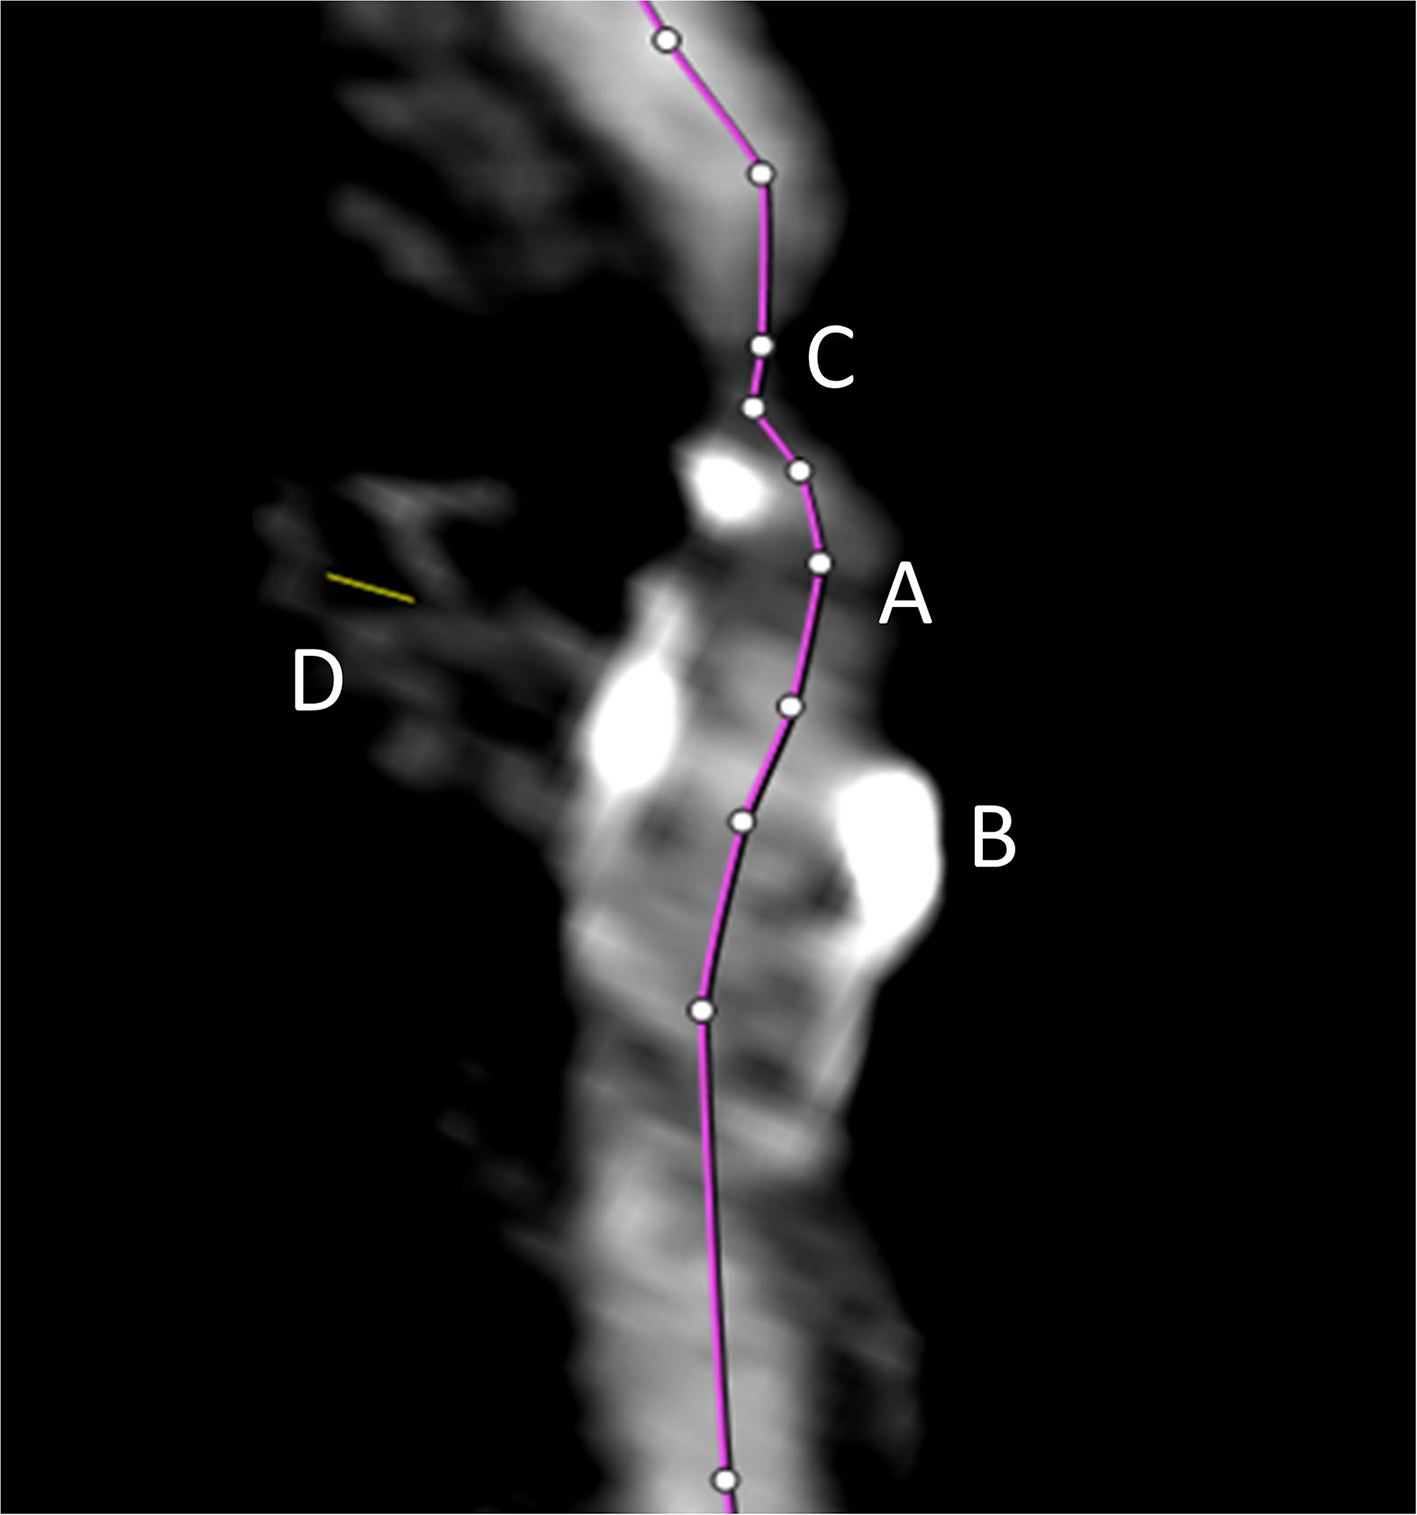

All semiautomated analyses were performed using an image analysis software (syngo.via, Siemens Healthineers, Forchheim, Germany, version VA30A) after preprocessing of the images including contrast optimization and determination of landmarks as previously described (14). This method automatically defined bilateral carotid artery centerlines and provided curved vessel reconstructions. Additional manual adjustments of these centerlines became necessary in case of severe pathologic changes of the stenotic segment, or data quality restrictions. Within the vessel reconstruction, the stenosis was localized and the minimum perpendicular caliber was determined. A second caliber was determined within the closest distal normal appearing ICA segment serving as the reference. The percentage of the stenosis area was finally computed (Figure 2). The center line needed to be adjusted if automatic segmentation of the target vessel failed because of insufficient luminal contrast, extensive calcification, pseudo-occlusion due to stenotic circulation decrement or accidentally in equal measure contrasted veins in proximate distance to the ICA. This was achieved manually by defining the start and end points of the vessel segmentation (Figure 3). The applied contouring algorithm was based on active contour models excluding calcification.

Figure 3

The automated vessel centerline fails in case of insufficient luminal contrast (A), the presence of extensive calcification (B), pseudo-occlusion of the vessel caused by stenotic circulation decrement (C), and in case of accidentally equally contrasted veins in striking distance to the artery (D). In such case, the centerline (purple line) needs to be adjusted manually.